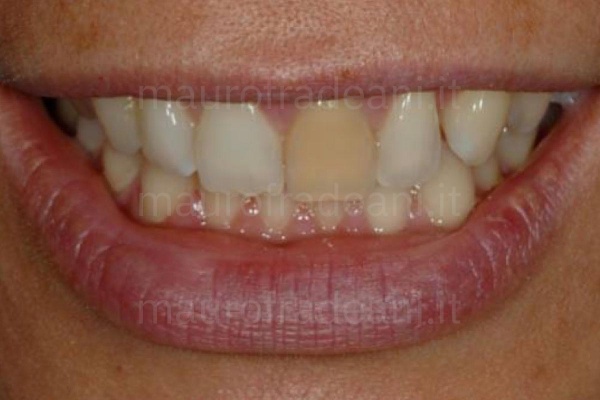

In-office dental bleaching: devitalized tooth

1/4: The left upper central is remarkably darker than the other dental elements, creating discomfort and dissatisfaction in the patient, who would like to harmonise the color of the smile.

Moreover, the reduced length of the right upper central tooth increases the patient's sense of unease.

2/4:

3/4: Thanks to the root whitening of the left central tooth and the restoration of the right central tooth in composite material, the esthetic appearance of the smile is significantly improved.

4/4: At the end of the treatment, the patient shows a remarkably harmonious and esthetically satisfying smile.